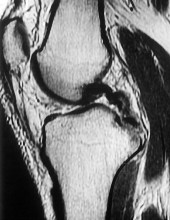

Question 12:

A 30-year-old woman presents with worsening knee pain. Radiographs reveal an eccentric, lytic, expansile lesion located in the epiphysis of the proximal tibia, extending to the subchondral bone. There is no sclerotic margin. Histology demonstrates mononuclear cells and numerous uniformly distributed osteoclast-like multinucleated giant cells. Which of the following is the most effective targeted medical therapy for advanced, unresectable cases of this tumor?

Correct Answer: Denosumab

Explanation:

The clinical and radiographic presentation is classic for a Giant Cell Tumor of Bone (GCTB). The neoplastic mononuclear cells in GCTB express high levels of RANKL, which recruits and activates the osteoclast-like giant cells, leading to massive bone destruction. Denosumab, a monoclonal antibody against RANKL, is highly effective in treating GCTB and is used for unresectable or recurrent lesions, or as a neoadjuvant therapy.